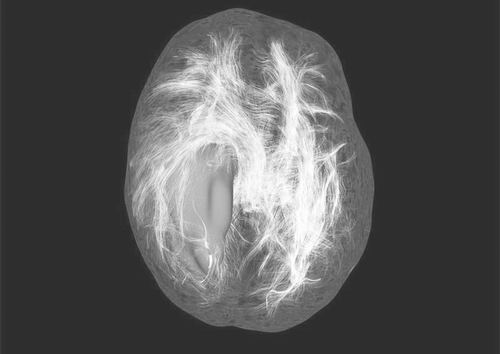

研究人员正试图增强抗癌病毒的效力,以期治疗包括脑肿瘤在内的疾病。图片来源:SPL